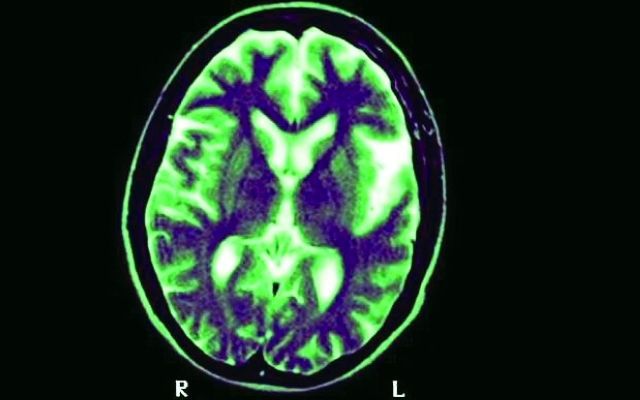

أظهرت دراسة جديدة أجراها باحثون في جامعة غلاسكو البريطانية أنه يمكن التخلص من أعراض الزهايمر، من خلال استعادة بروتين مفقود في أدمغة المرضى المصابين بالخرف.

وخلال تجاربهم على الفئران، أظهر الباحثون البريطانيون أن رفع مستويات بروتين «IL-33» يدفع جهاز المناعة، للتخلص من صفائح الأميلويد، التي يتسبب تراكمها في منع الخلايا الدماغية من التواصل مع بعضها بعضاً، ويأمل الباحثون إجراء تجارب إكلينيكية على البشر قريباً.